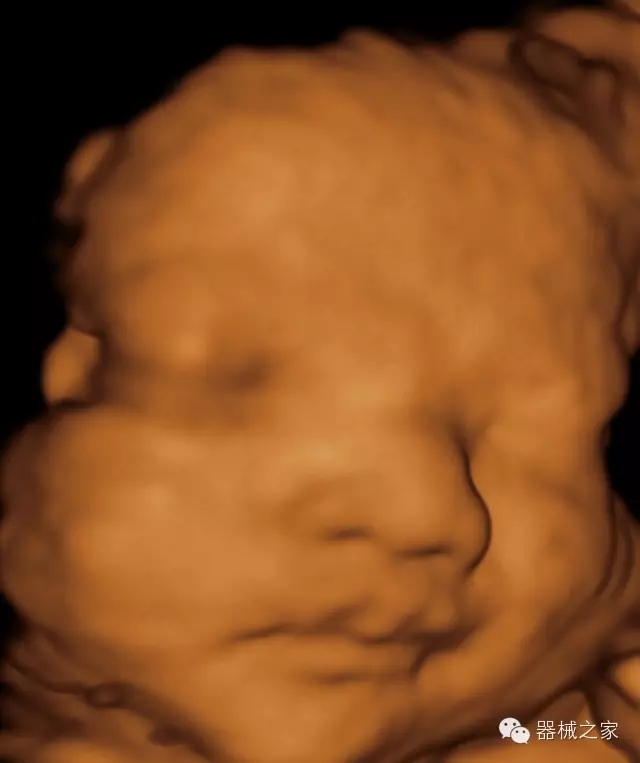

臨床圖片賞析

·完整的3D/4D臨床應(yīng)用,STIC, MCUT 和Auto NT等滿足產(chǎn)科所有應(yīng)用;

·更高的HQ羊膜腔鏡成像技術(shù)精細(xì)觀察每一個暗區(qū)細(xì)節(jié);

·智能的觸摸屏界面,能任意角度方位旋轉(zhuǎn)3D圖像,以及注釋快速標(biāo)記,提供直觀與便捷的操作,提高了工作效率;